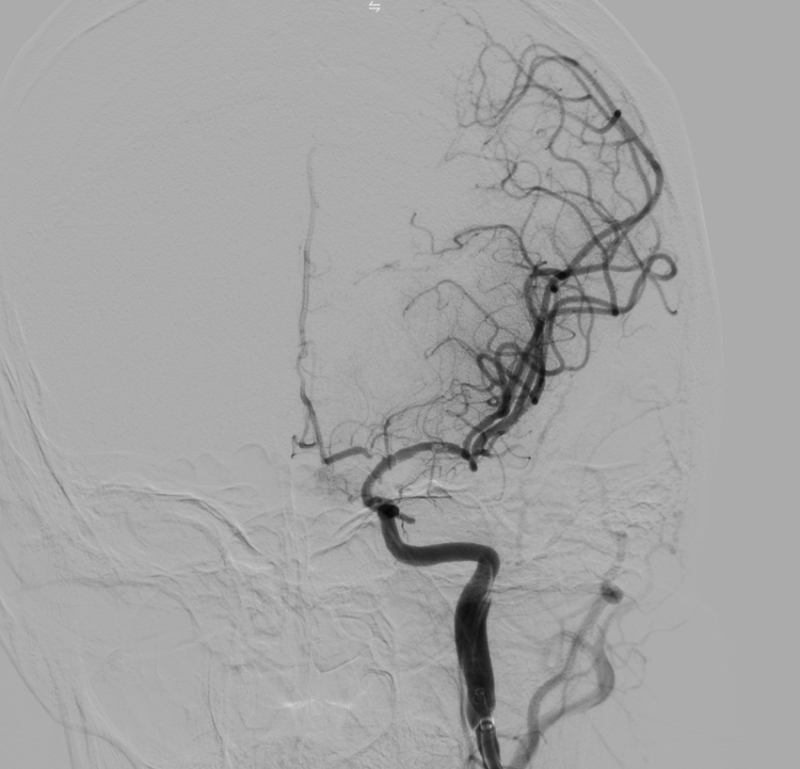

Kết quả chụp DSA xác định tắc động mạch não giữa trái đoạn M1 do hẹp nặng. Kíp can thiệp đã tiến hành nong bóng tái thông mạch máu, khôi phục dòng chảy lên não thành công.

Hình ảnh: DSA sau can thiệp tái thông TICI 3

Kíp can thiệp do Th.bác sĩ Giáp Hùng Mạnh, Trưởng khoa Thần kinh VLTL-PHCN, Bệnh viện Bãi Cháy cùng ê kíp thực hiện. Sau can thiệp, tình trạng người bệnh ổn định, tỉnh táo hơn, cải thiện vận động, sức cơ chân phải đạt 3/5, huyết áp 110/70 mmHg và đang tiếp tục được theo dõi, điều trị tại bệnh viện.